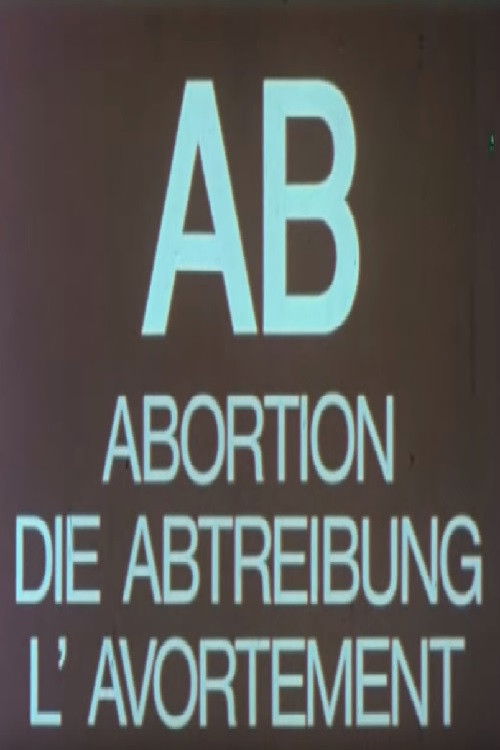

Bloß keine Tochter!

Almost 200 million women are "missing" in Asia - the result of targeted abortion of girls and dubious population policies. An investigative documentary about women who are not allowed to have daughters, about desperate attempts by men to find a wife somewhere, and about the abuse of women as pawns of politics and business.